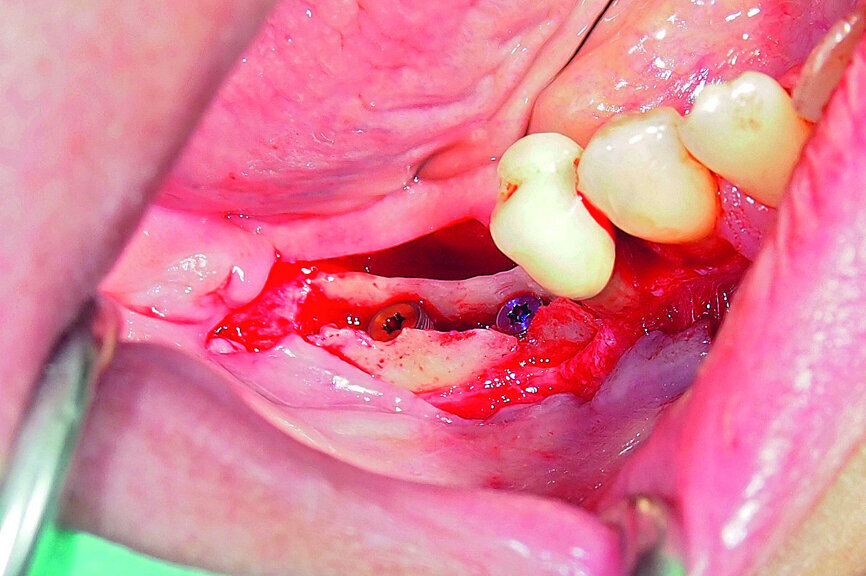

Fig. 15: Combination of full- and partial-thickness flap elevation.

Fig. 16: Mandibular ridge splitting with vertical cuts.

Fig. 17: Creation of space in between the buccal and lingual lamina with the intact attached periosteum on the buccal.

Fig. 18: Placement of two GC Aadva Standard implants with regard to the future restorative margins.

A demonstration of this technique is shown in Figures 13 to 20. This case presents an elderly woman who had lost her teeth in the lateral mandible decades ago. Being a healthy non-smoker with good oral hygiene, no history of periodontal disease and low masticatory forces, she was an adequate candidate for bone grafting together with implant placement. The future restorative margins allowed the usage of ridge splitting (Figs. 13 & 14). Therefore, we opted for a ridge split with vertical releases carried out utilising a partial-thickness flap. The periosteum was left attached in order not to impede the perfusion of the buccal plate (Fig. 15). After ridge splitting, the buccal and lingual plates were separated with the use of bone spreaders (Split-Control Plus, Meisinger) to allow the placement of two GC Aadva Standard implants, one of 3.3 mm in diameter and 8.0 mm in length and the other measuring 4.0 mm in diameter and 8.0 mm in length (Figs. 16–18).